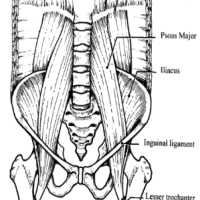

A 42-year-old South Asian woman with a history of hypothyroidism and recurrent UTIs presented with a 2-week history of lower abdominal pain radiating to both lower limbs, associated with high-grade intermittent fever. The pain was spontaneous in onset, progressive, and unrelated to trauma. She had previously received multiple short courses of antibiotics for recurrent UTIs. She presented to our center 10 days after the onset of symptoms. On evaluation, she was febrile (temperature 102°F), with suprapubic tenderness and restriction of active and passive hip movements bilaterally. Initial laboratory investigations revealed neutrophilic leukocytosis (total leukocyte count: 15,000/µL; neutrophils: 13,600/µL) and elevated C-reactive protein (195 mg/L). Urine routine examination demonstrated numerous red blood cells but no pyuria. A contrast-enhanced computed tomography renal stone survey showed perinephric stranding in the retropubic space suggestive of cystitis, with no evidence of collections, hematoma, or pelvic bone fractures. She was empirically started on intravenous piperacillin-tazobactam for presumed acute cystitis, given her history of recurrent UTIs. However, urine culture showed no growth after 48 h, while blood cultures grew MRSA. Antibiotics were escalated to intravenous teicoplanin (400 mg twice daily). Despite 48 h of appropriate therapy, she continued to have high-grade fever and worsening excruciating suprapubic pain radiating to the groin and medial thighs, severely limiting her mobility. Magnetic resonance imaging (MRI) of the pelvis with contrast revealed osteomyelitis of the bilateral pubic bones and superior pubic rami, with abscesses (10 mL and 1.5 mL) around the pubic symphysis, fluid collections in the right adductor and obturator externus muscles, and edema of the obturator internus, externus, and pectineus muscles (Figs. 1, 2, 3, 4).

Figure 1: Axial T2-weighted magnetic resonance imaging of the pelvis showing marrow edema and signal alteration involving the bilateral pubic bones and superior pubic rami, consistent with osteomyelitis.